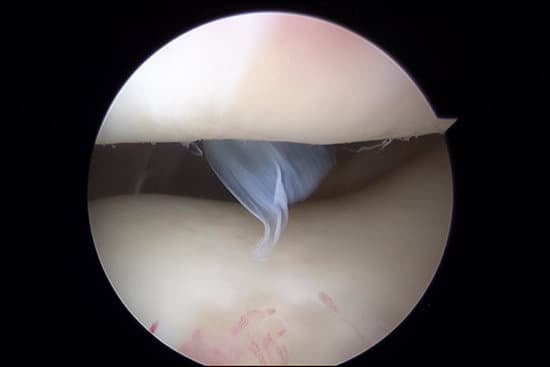

관절경 검사: 내시경을 이용해 관절 내부를 직접 확인하며 진단과 치료가 동시에 이루어질 수 있습니다.

관절경 수술: 손상된 연골을 제거하거나 수리하며, 관절 내부를 깨끗하게 정리합니다.